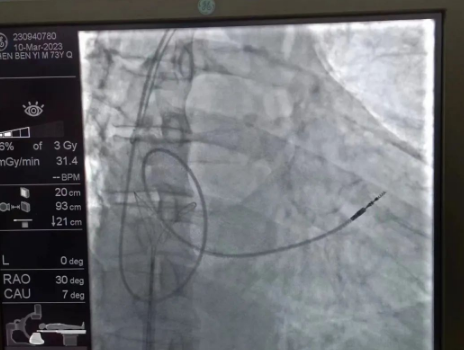

術(shù)中,孫書紅醫(yī)師首先切開起搏器囊袋,游離出起搏器脈沖發(fā)生器,發(fā)現(xiàn)起搏電極完全斷裂,連接于起搏脈沖發(fā)生器,殘端約10cm;考慮患者為起搏依賴患者,需再次植入新的起搏電極導(dǎo)線,穿刺了腋靜脈,放置導(dǎo)絲;同時(shí),李偉杰教授穿刺了左、右股靜脈,于右股靜脈置入了”抓捕器”,左股靜脈備用臨時(shí)起搏通路,以防術(shù)中出現(xiàn)心跳驟停。為了準(zhǔn)確抓捕到心房內(nèi)的在逃起搏電極,李偉杰教授將導(dǎo)管室的X光機(jī)球管調(diào)整成了冠脈模式,這就意味著在抓捕過程中,醫(yī)生要比平時(shí)的手術(shù)“吃”更多射線……

在透視模式下,抓捕全憑醫(yī)生的經(jīng)驗(yàn)與手感,一次次嘗試,一次次失敗,在場外觀摩手術(shù)的醫(yī)生同樣為李偉杰教授捏了一把汗,“找到了!”電子屏里抓捕器向在逃起搏電極“發(fā)起進(jìn)攻”,一把逮住并順利拔出一根長達(dá)58cm的起搏電極。